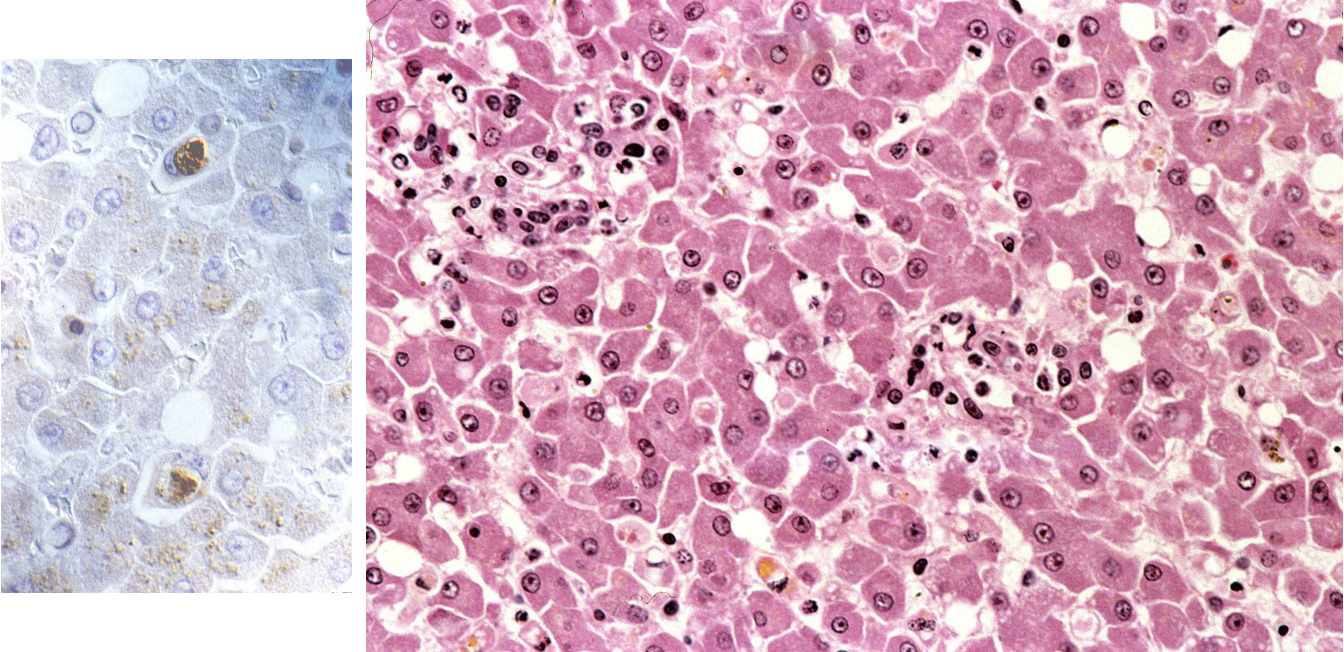

What is being shown in this image

Acute hepatitis

Neutrophils dom = blue arrows

Mononuclear cells

Pigment = bile —> extracellular

bile stasis in caniculi

Lymphos & macros also

Necrosis during acute hepatitis

Increased leukocytes in sinusoids (diffuse)